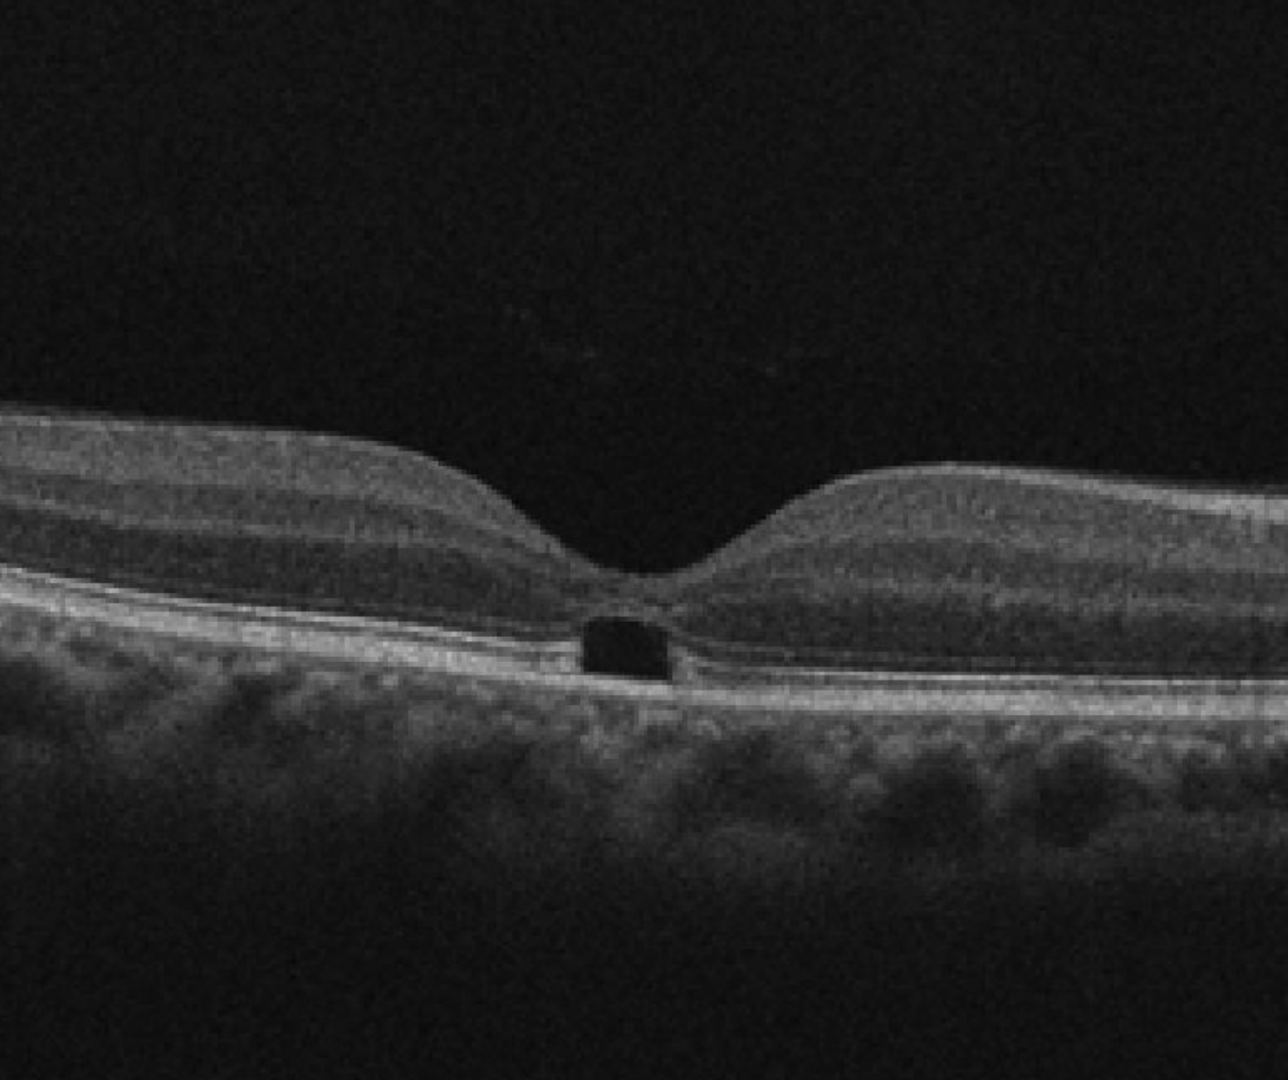

Clinically, bilateral yellow dots may be seen at the fovea. This corresponds to changes in the outer retinal layers on OCT which may be either hyper-reflectivity of the ellipsoid zone or a subfoveal hypo-reflectivity. Fundus autofluorescence is typically normal.

Case 1: Presumed Popper Maculopathy

A 56 year old Middle Eastern male with a long history of drug use and reduced vision. He denies any history of sun gazing or watching eclipses.